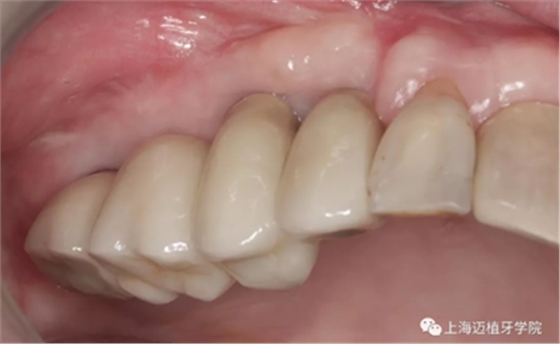

戴牙